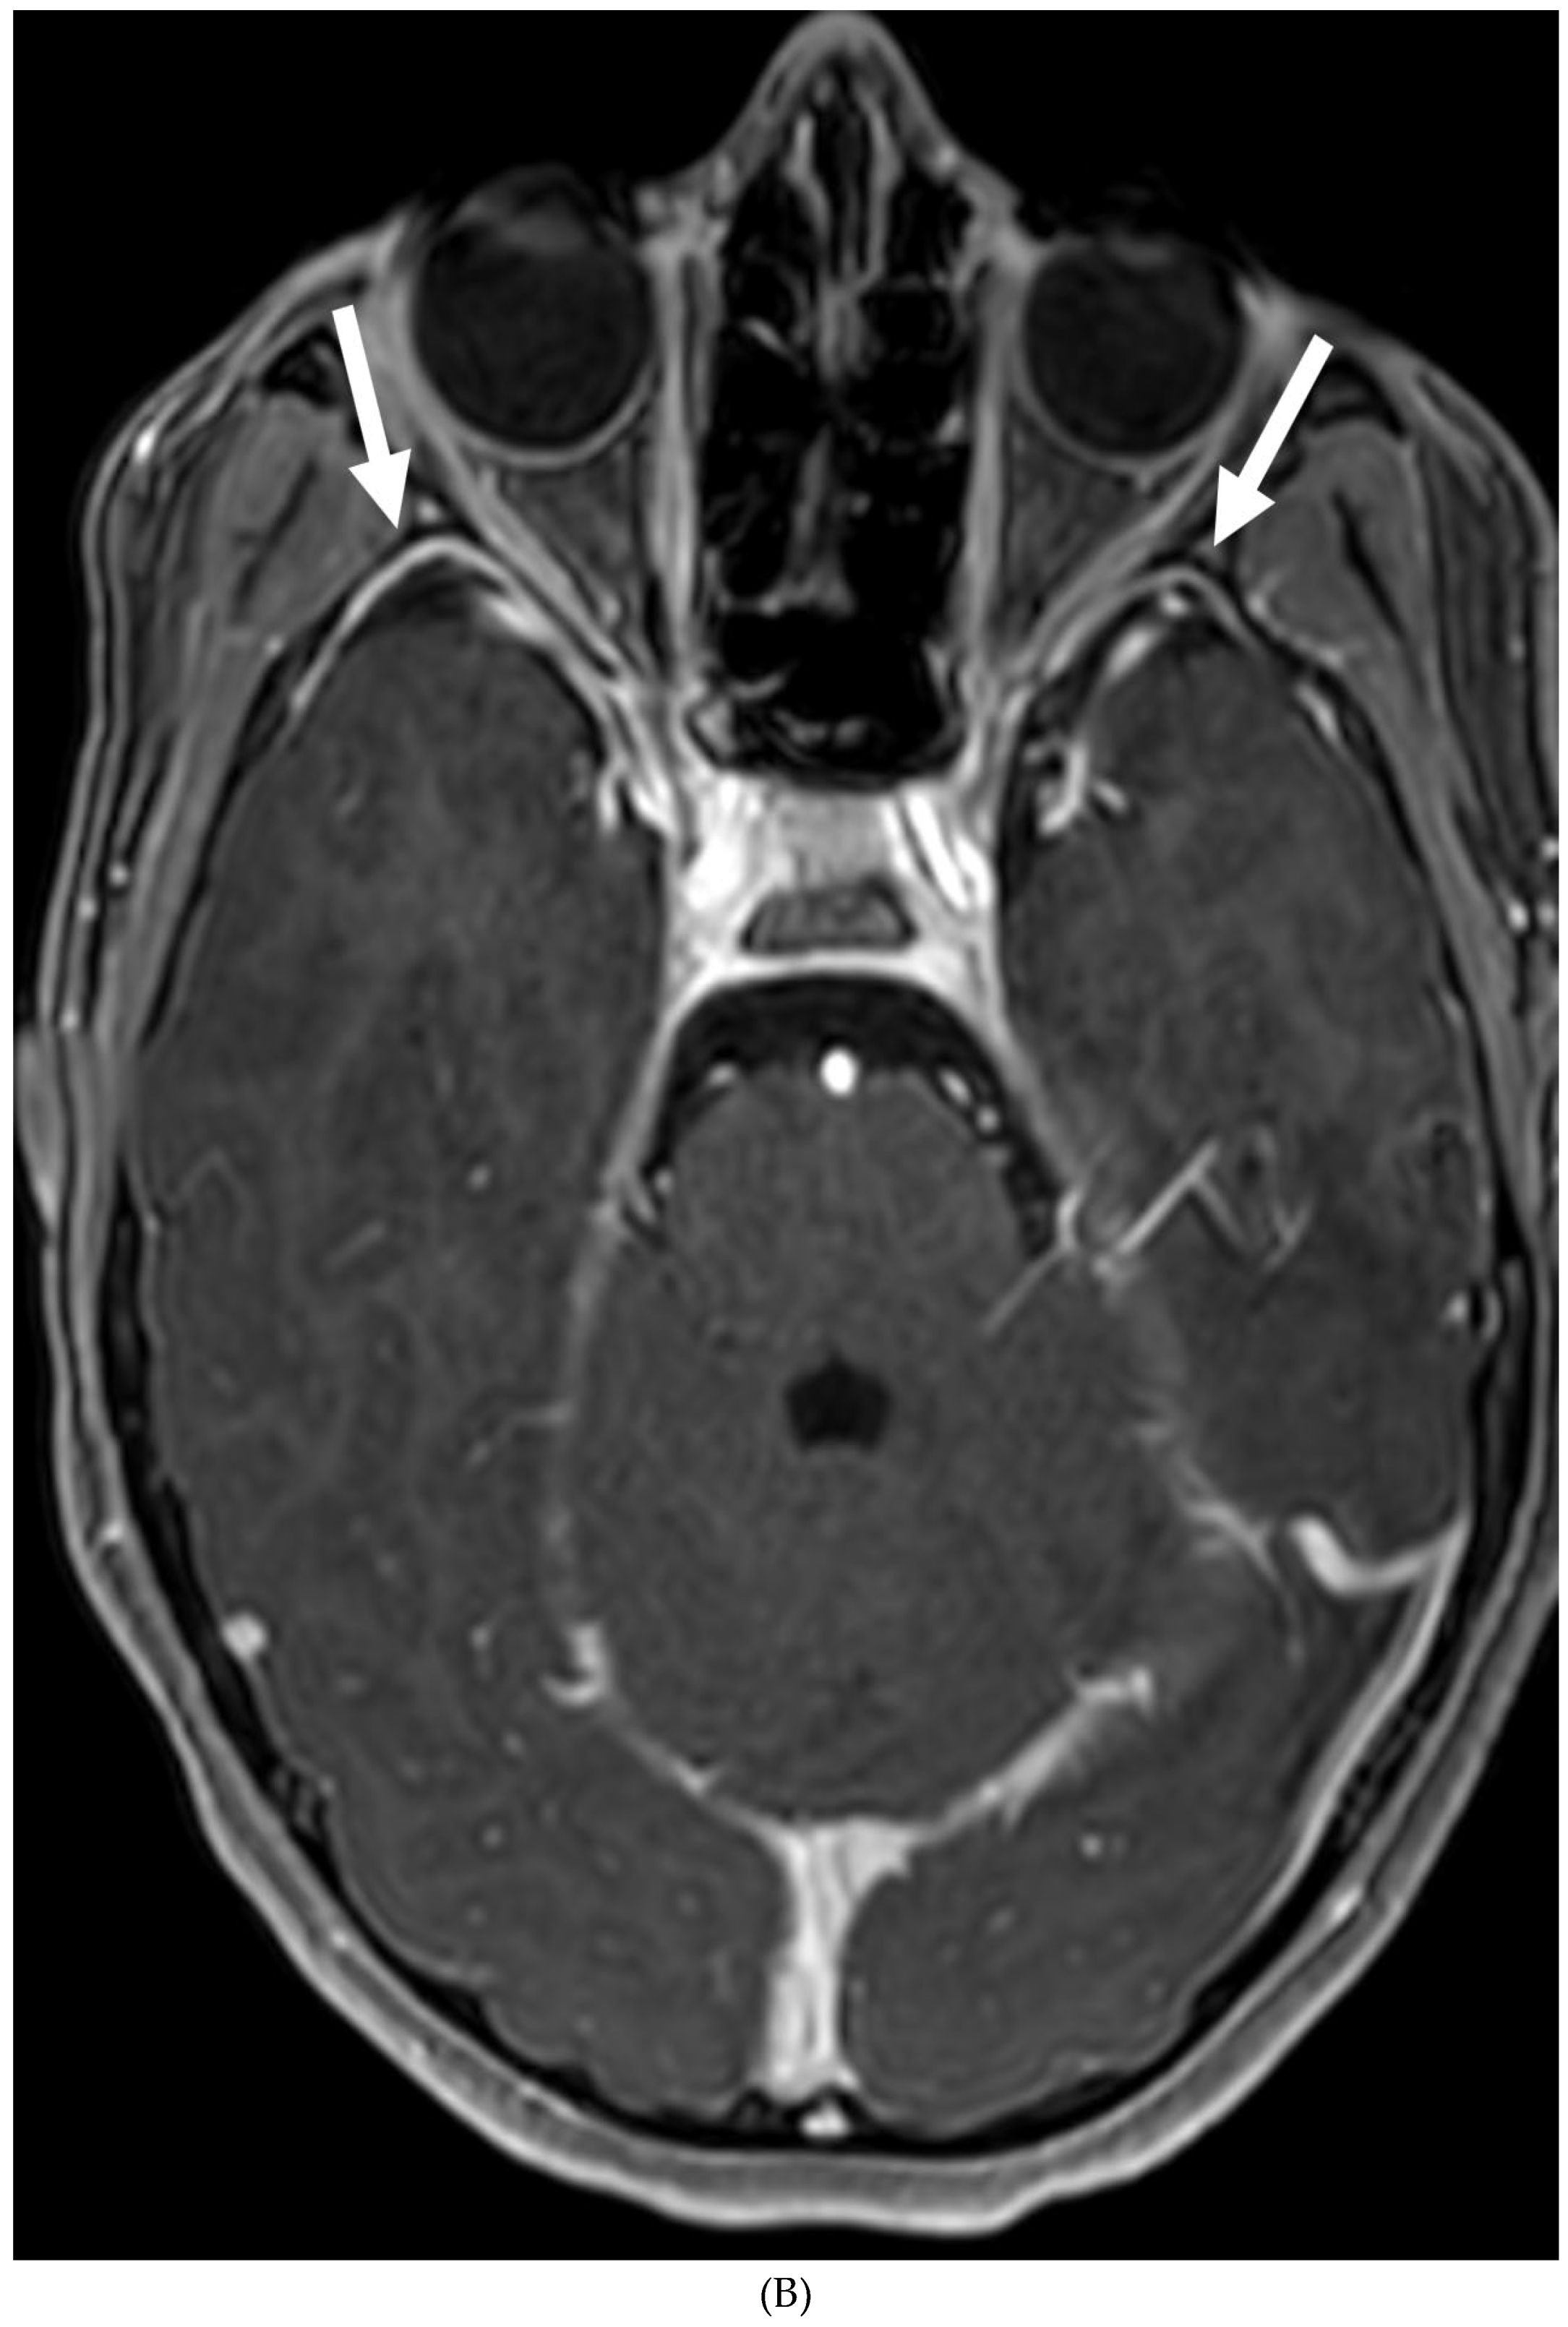

MOYA MOYA